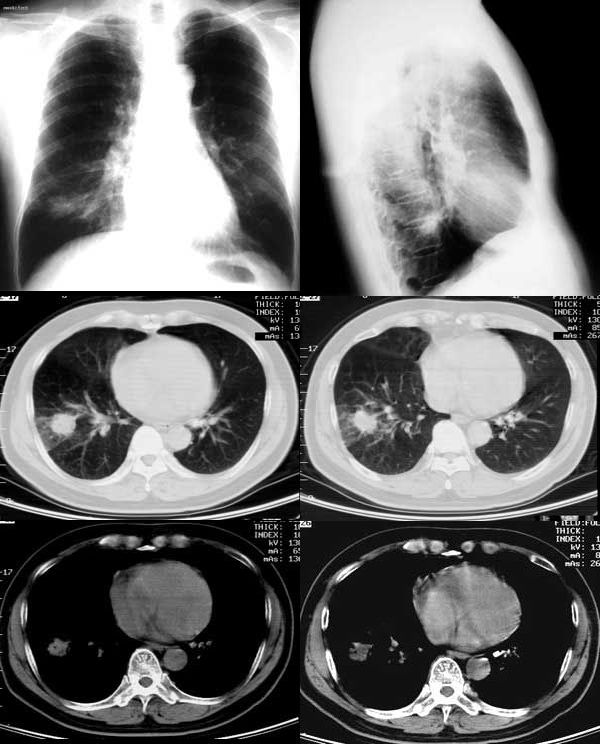

病例一,男,58岁,胸痛半月余

病例二,男,63岁,咳嗽、低热月余。

②ct249:由gaozhengyi版主提供

http://www.radida.com/radinet/read.php?tid=654&page=1

患者女,65岁,主因低热、咳嗽、痰中带血丝一周多来院。

继续抗炎治疗后复查病变进一步缩小。可惜未留下图片。但抗炎前后的片子对比已能证实为炎性病变。

③35岁女性,因颈部包块术前检查发现右下肺圆形结节。

④男性,65岁,咳嗽、咳痰3月。

⑤男性,45岁,咳痰,痰中带血。

⑥男性,45岁。一个月前开始咳嗽。

⑦女性36y,胸痛2周住院。 手术后病理为:炎性假瘤。